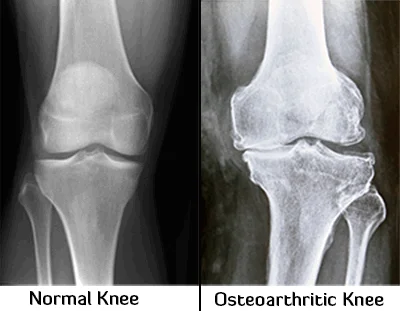

Osteoarthritis (OA) is a degenerative joint disease characterized by the gradual degradation of joint cartilage due to wear and tear. As the slippery tissue that coats the ends of your bones wears away, it causes friction, pain, and stiffness. Frequently seen in Kolkata among adults over 60, OA commonly affects the knees, hips, and spine. Dr. Manoj Kumar Khemani specializes in managing OA through personalized non-surgical and surgical protocols to Restore Your Quality of Life.

Pain in the affected joint is the commonest symptom. Joint pain of osteoarthritis is usually worse later in the day. There can be swelling, warmth, and creaking noise in the affected joints. Similar symptoms of joint inflammation can also occur due to metabolic conditions like uric acid crystal deposition in joints, which require a different line of treatment. Pain and stiffness of the joints can also occur after long periods of inactivity (for example, sitting in a theater, getting up from bed in the morning etc.).

In severe osteoarthritis, there can be pain even at rest or pain with limited motion and walking can become extremely difficult. OA in the fingers and hands can limit fine movements. In the spine it can cause persistent neck or back pain.